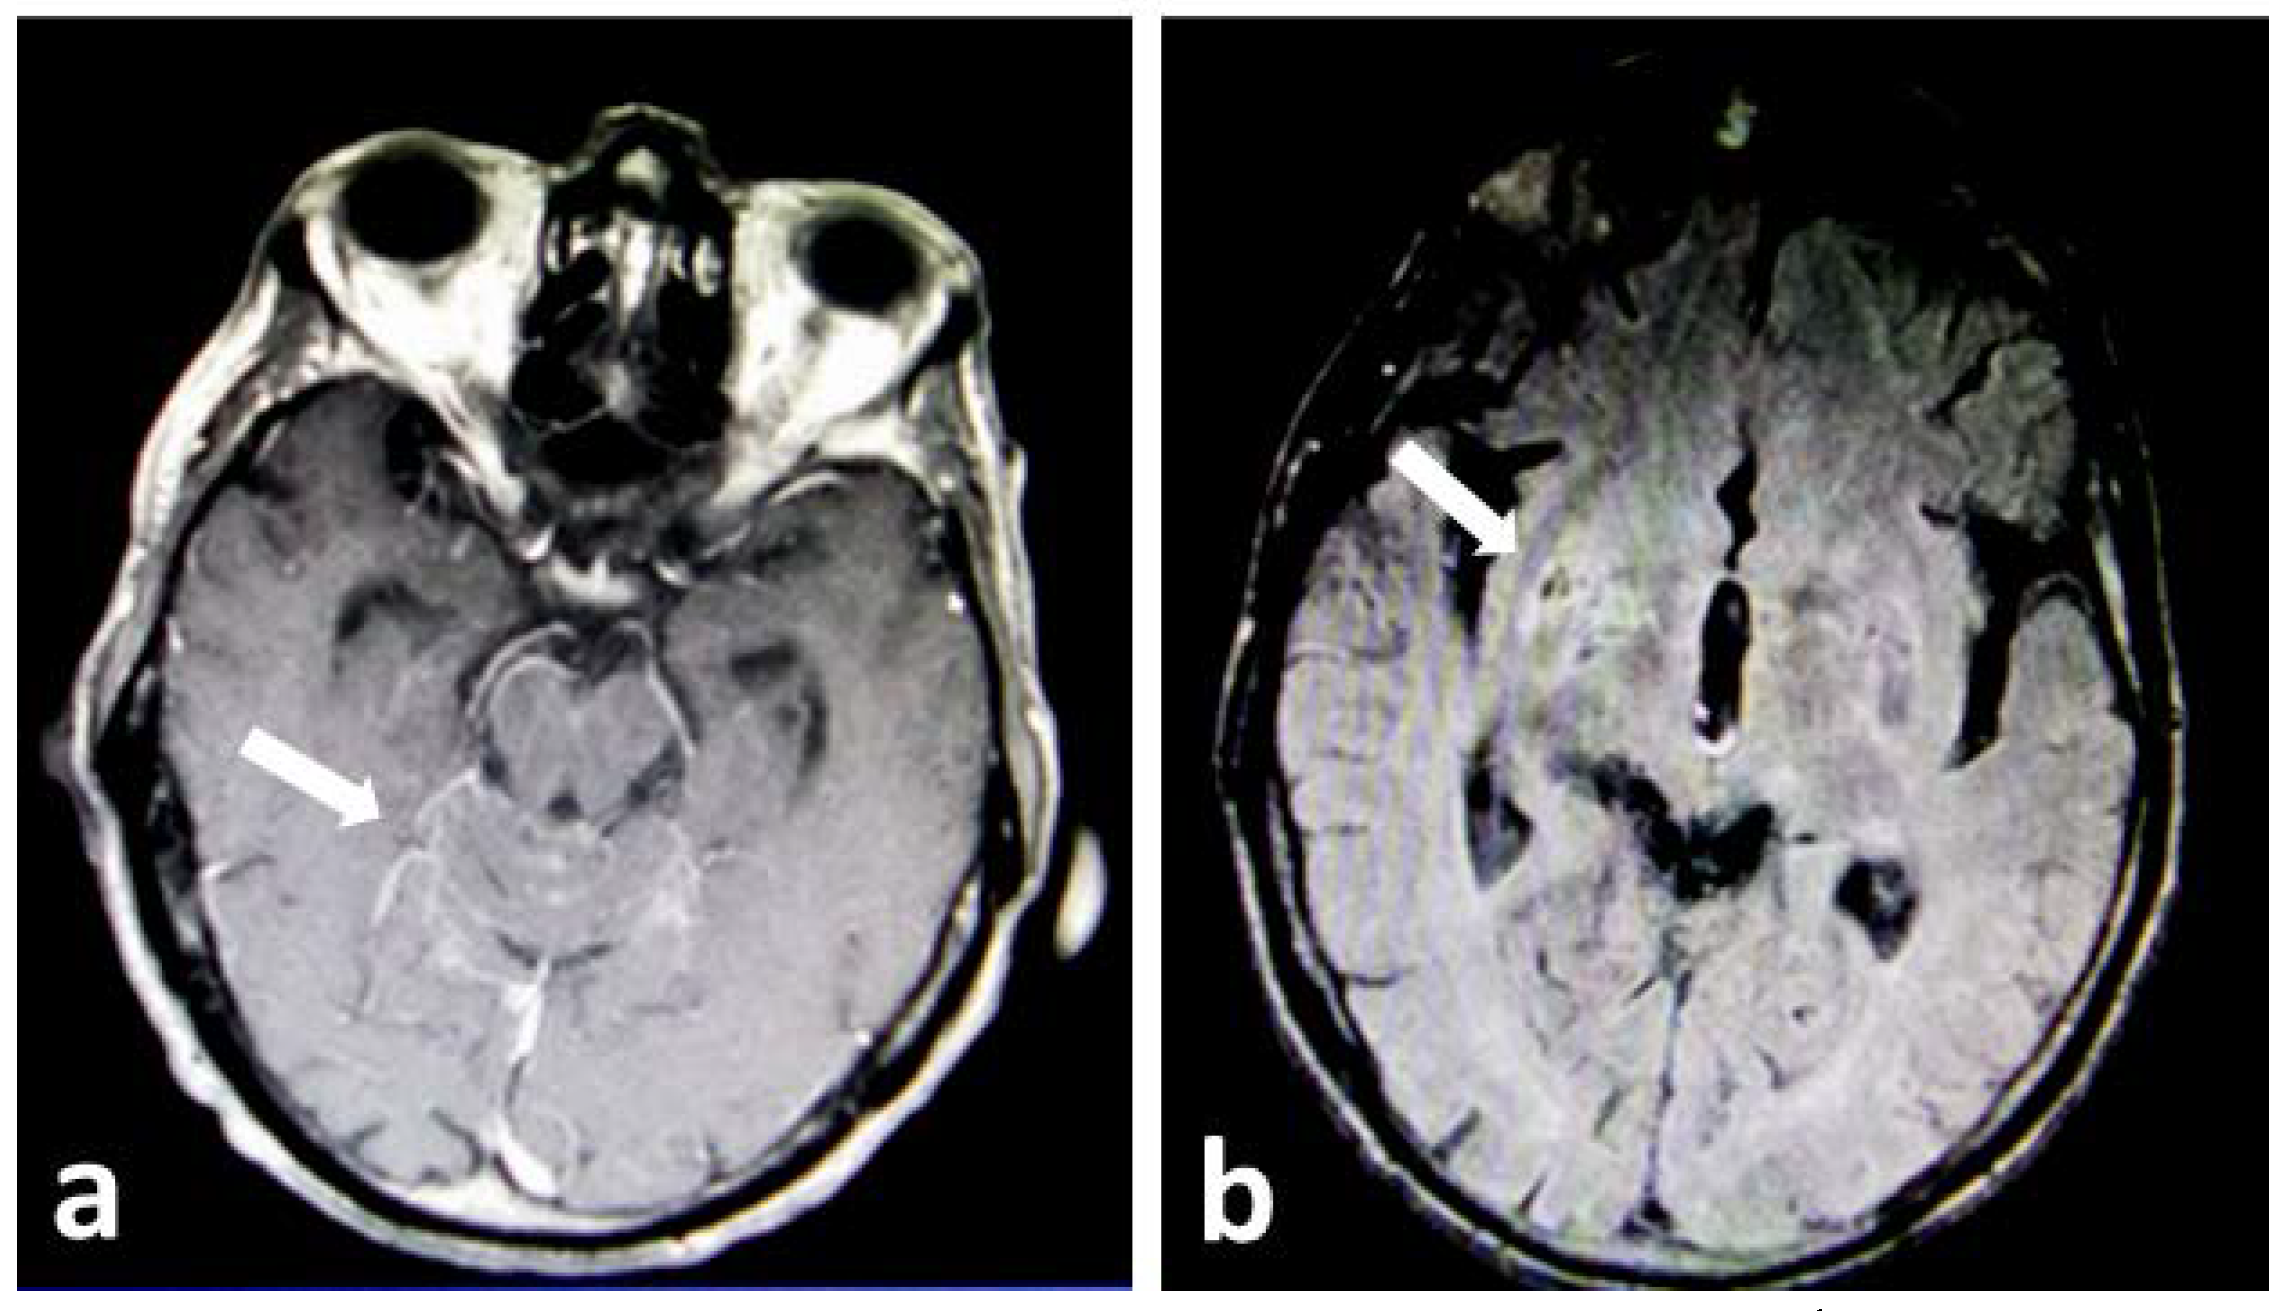

Based on the patient’s history (cryptococcal skin infection by a fluconazole-resistant strain), treatment was initiated with intravenous liposomal amphotericin B (4 mg/kg) and IV flucytosine (25 mg/kg every 6h). HIV antibodies tested negative and T cell subset determination in peripheral blood revealed normal CD3+CD4+/CD3+CD8+ T cell ratio and an increased number of NK cells. The patient’s clinical condition deteriorated within 4 days with loss of vision and intense neck rigidity. Repeated magnetic resonance imaging of the brain revealed lesions compatible with infectious meningoencephalitis (abnormal leptomeningeal enhancement in the frontal, parietal and posterior cranial fossa and dilated perivascular spaces in the bilateral basal ganglia; Figure 1a,b). Despite continuous antifungal therapy the patient died one week after initiation of treatment. The relatives of the patient gave us written informed consent to publish this case.

Figure 1.

Brain magnetic resonance images in the advanced stages of the disease showing a. abnormal leptomeningeal enhancement in the posterior cranial fossa (white arrow) and b. dilated perivascular spaces in the bilateral basal ganglia (white arrow pointing to the lesions on the right hemisphere). At the time when the scan was performed, the patient had severe neck rigidity and loss of vision.